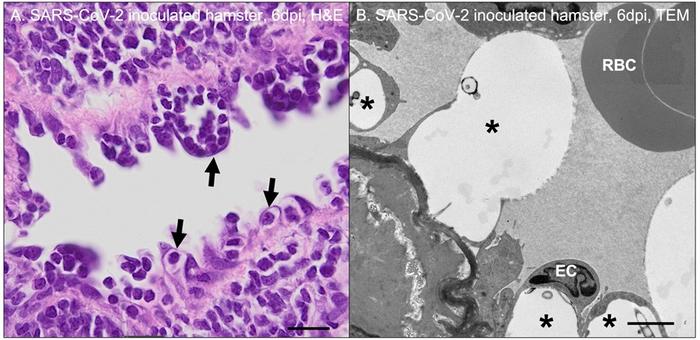

As the pandemic progressed, physicians frequently reported clinical evidence of coagulation abnormalities and microscopic indicators of pulmonary vascular damage associated with severe human cases of COVID-19, noted Erin E. Ball, DVM, PhD, Department of Pathology, Microbiology, and Immunology, University of California, Davis, and colleagues. A team of investigators led by Dr. Ball injected severe acute respiratory syndrome coronavirus 2 ( SARS CoV 2) that causes COVID-19 into a Syrian golden hamster model of human COVID-19 to determine the cause of pulmonary vascular damage. At three to seven days post inoculation, they detected SARS-CoV-2 antigen and RNA within airway epithelial cells, pneumocytes, and macrophages, but not associated with blood vessels.

Their results showed that regions of active pulmonary inflammation in SARS-CoV-2 infection were characterized by ultrastructural evidence of endothelial damage with platelet marginalization and perivascular and subendothelial macrophage infiltration. SARS-CoV-2 antigen or RNA was not detectable within affected blood vessels. The investigators had initially assumed the prominent microscopic vascular lesions noted in hamsters between three and seven days post SARS-CoV-2 inoculation would be the result of direct viral infection of cells comprising blood vessels; however, this was not the case.

Dr. Ball added, These findings suggest that indirect vascular damage, possibly secondary to immune dysfunction, is a major contributor to vascular damage observed in SARS-CoV-2 - inoculated hamsters and potentially severe COVID-19 infection in humans . Immune dysregulation resulting in excessive production of pro-inflammatory cytokines, endothelial damage, and platelet hyperactivation is a plausible driving force behind the hypercoagulable state and microthrombosis observed in some COVID-19 patients.”